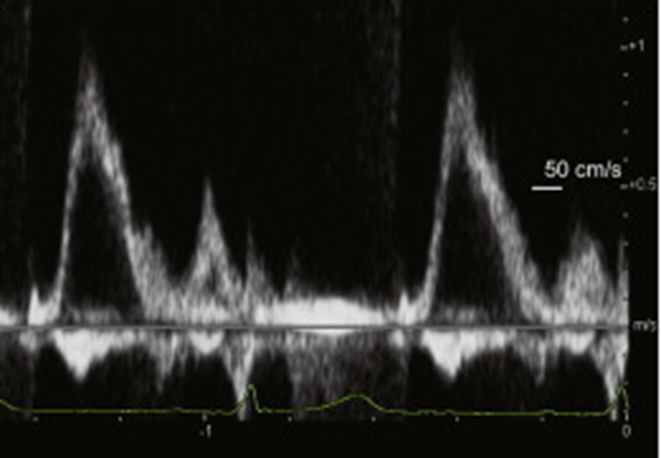

Normal hepatic vein flow travels _____ from the transducer towards the IVC and is encoded in _____

away/ blue.

TR flowing into the IVC & Hepatic veins will flow ______ the transducer during systole and is encoded in _____

towards/red

On the spectral waveform, this systolic flow will appear _____ the baseline (______)

(color & spectral flow reversal of the hepatic veins)

above/ antegrade

The hepatic vein waveform can be reflective of the ______

severity of TR present.

The more severe the regurgitation, the more _______ the hepatic waveform becomes.

pulsatile

anything above baseline means flow reversal

How to prove severe TR